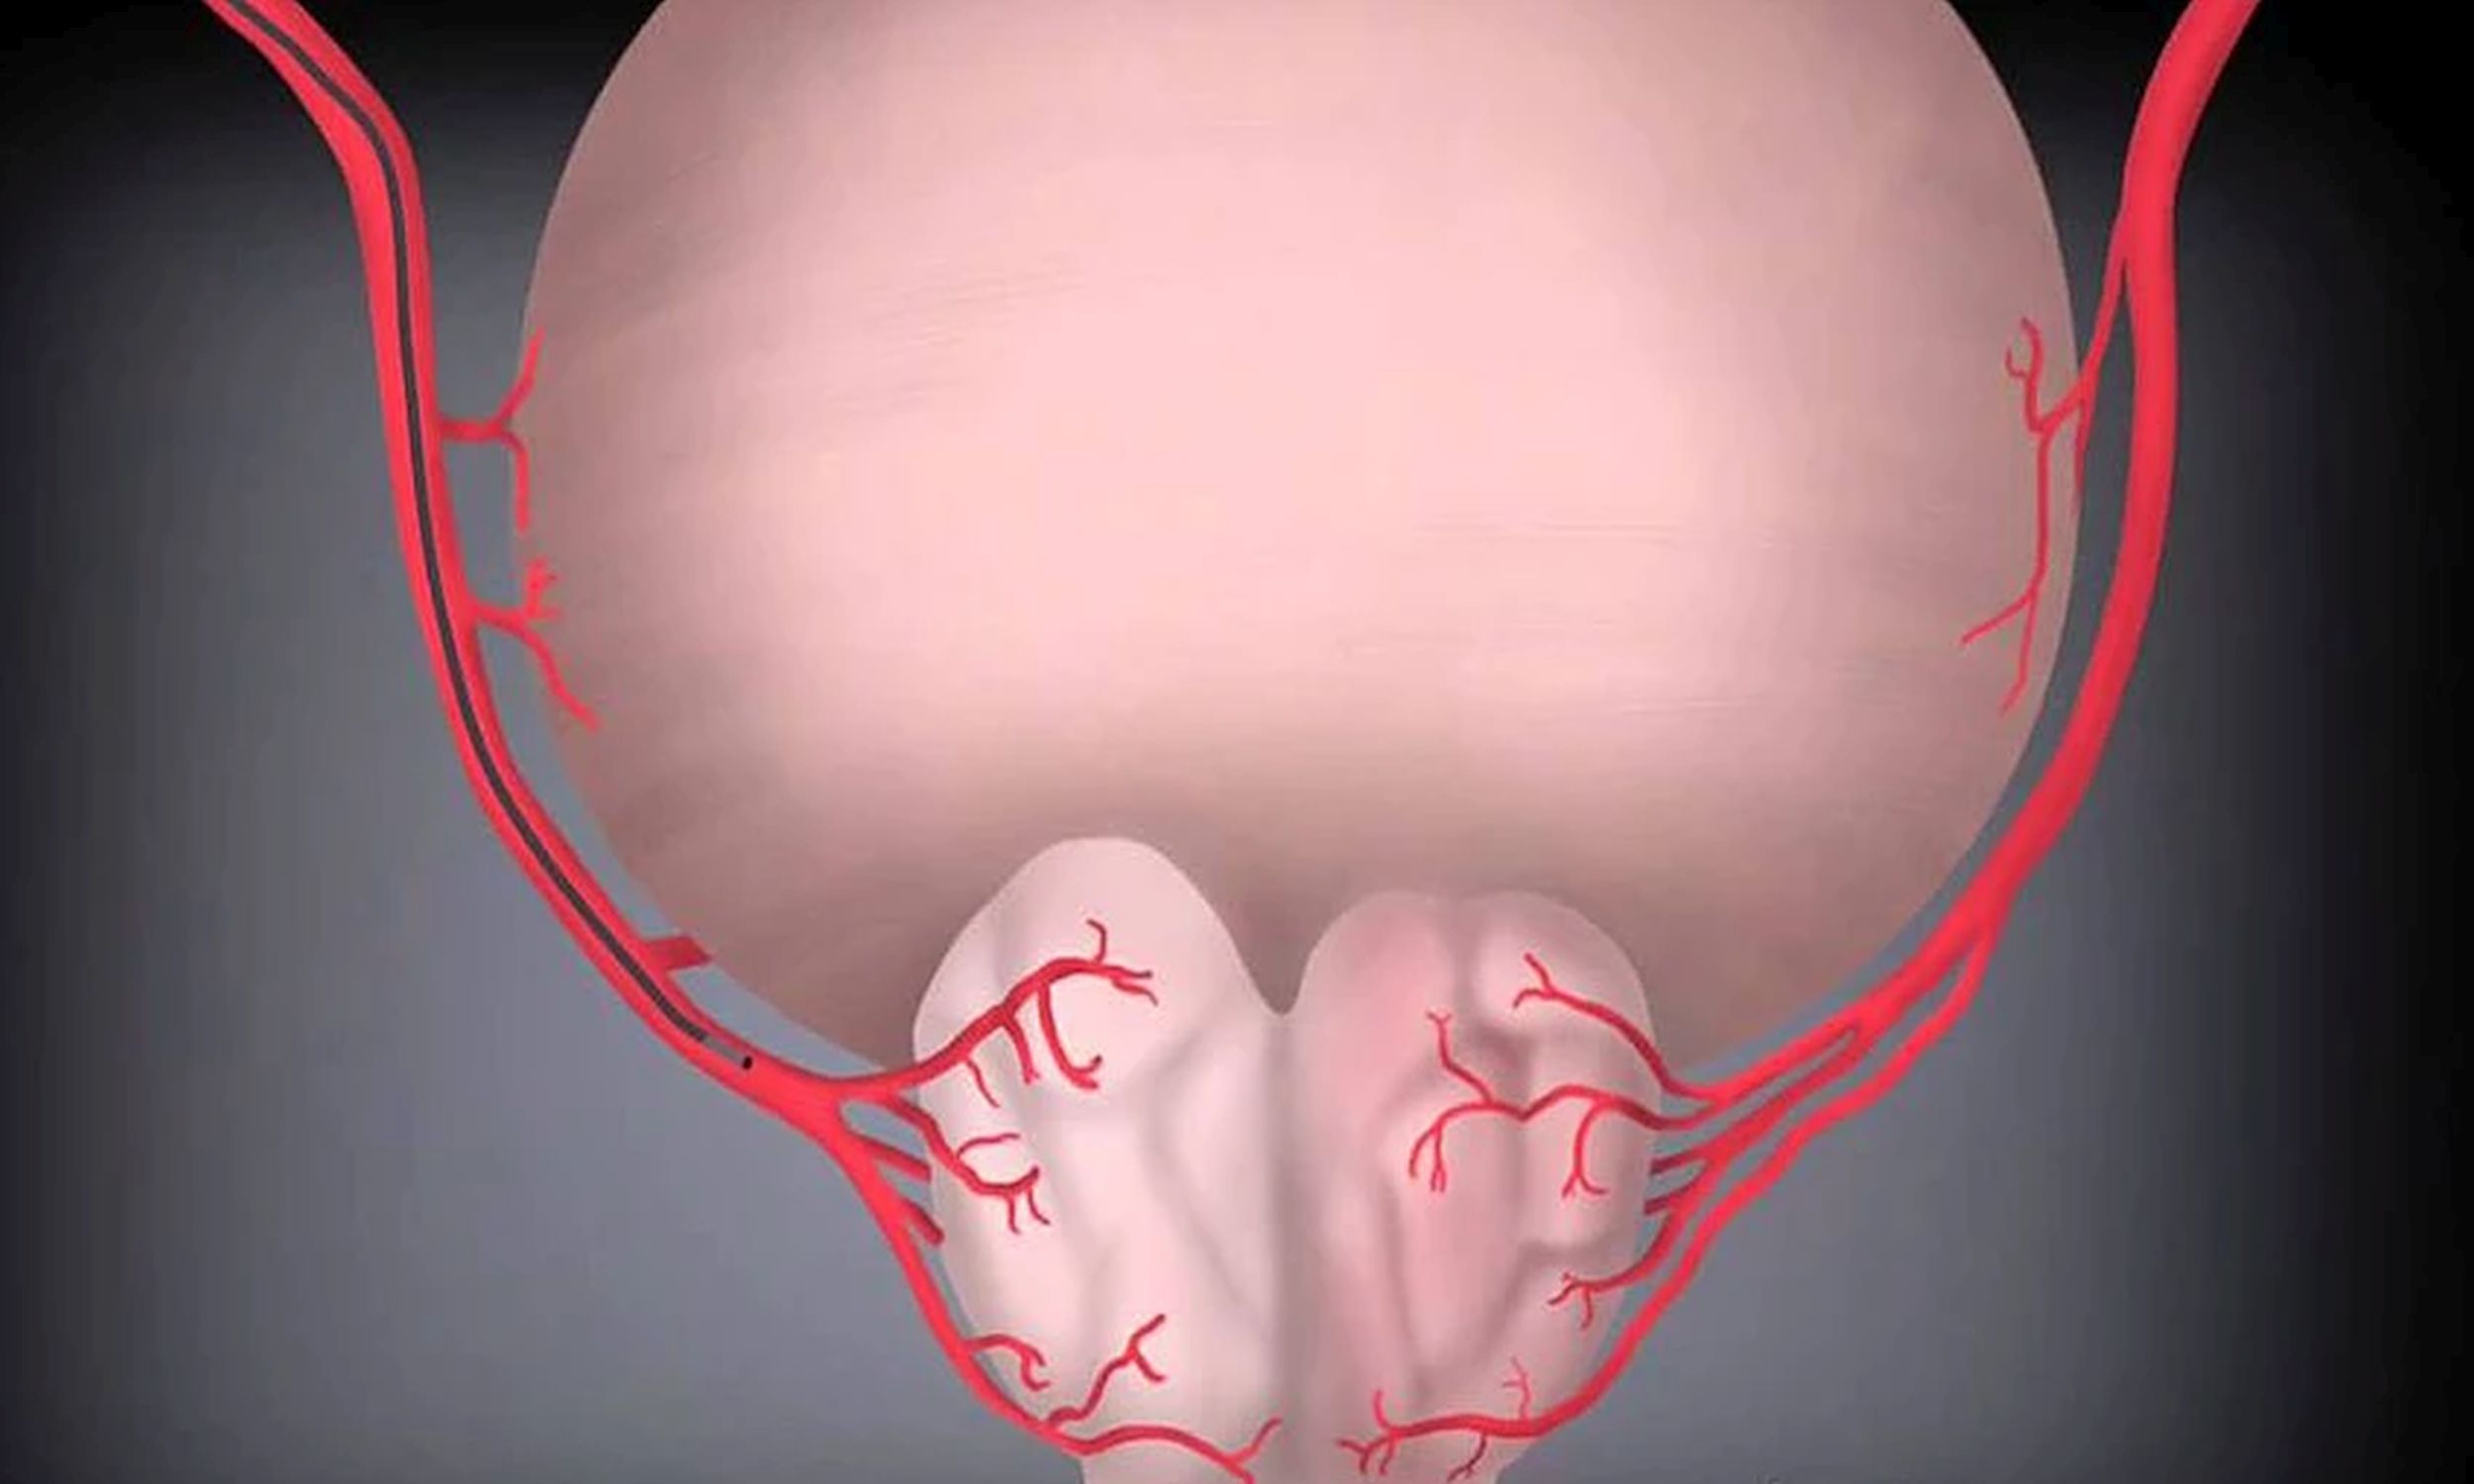

мболизация яичковой

Эмболизация яичковой 115 фото